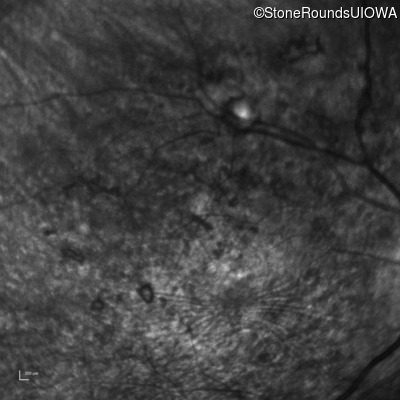

Infrared Fundus Photograph - Right - 10/700 sc

Exemplar